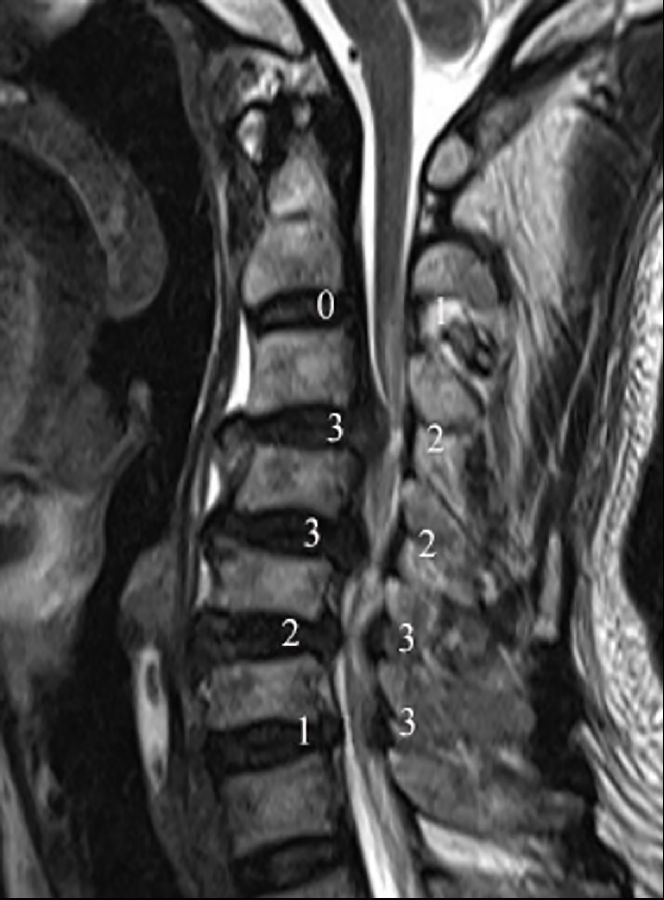

3.4 颈脊髓压迫指数

颈脊髓压迫指数是在颈椎MRI矢状位像上测量所得。依据前方间盘及后方黄韧带导致硬膜囊受压程度,对硬膜囊受压比例进行分级,前方和后方分别评-3分(图3)。依据评分结果分为3度(正常/轻度,中度,重度)。其中,中度或重度受压定义为明显受压,记录受压节段数量。

图3.颈椎MRI矢状位颈脊髓压迫指数评估方法。依据前方及后方硬膜囊受压程度,对硬膜囊受压比例进行评估